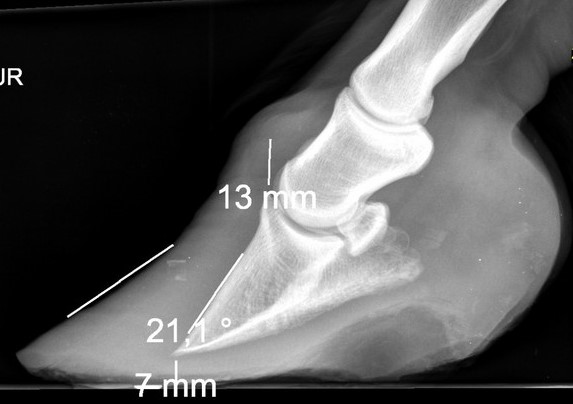

• L’inflammation et la perturbation du réseau sanguin dans le pied va provoquer la séparation des lamelles du podophylle et du keraphylle. La 3 phalange n’est alors plus « tenue » par celles-ci et perd sa cohésion avec la paroi du sabot.

• La conséquence est rapide, la 3e phalange va alors basculer vers l’avant.

• Si la fourbure n’est pas gérée rapidement, la phalange va continuer de descendre jusqu’à venir percer la sole, par effondrement de la colonne osseuse